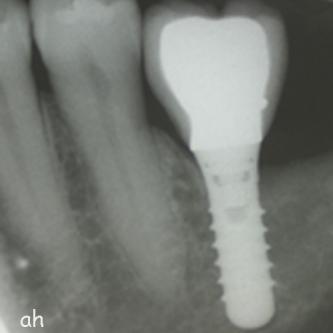

Exemple 2: Un implant remplaçant la racine d'une molaire inférieure gauche.

Exemple 2: La couronne en céramique scellée sur cet implant.